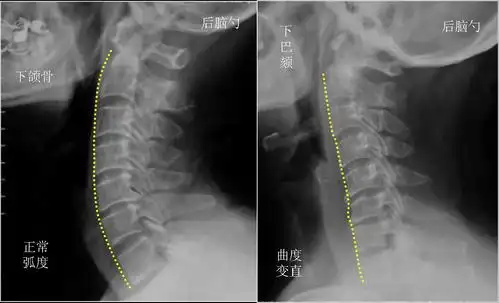

什么是健康颈椎该有的生理曲度,你颈椎还健康吗?

颈椎生理曲度

颈椎生理曲度是指第45颈椎向前凸出的弧度,某些原因引起弧度消失时